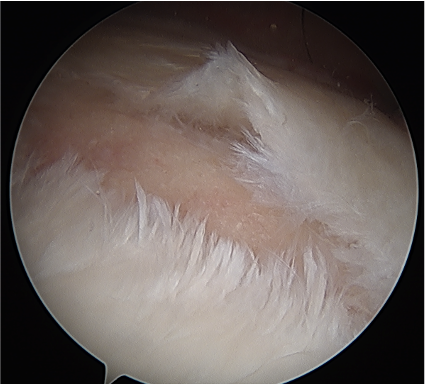

Glenohumeral joint approach

Arthroscopy techniques spinoglenoid cyst decompression

Vumedi spinoglenoid cyst decompression video

Posterior glenohumeral capsulotomy and cyst decompression